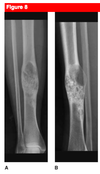

16yo female with painful thigh. Top Diagnosis? How will she present to you? Radiographic findings typical of this?

Ewing Sarcoma

-

Presentation

- pain often accompanied by fever

- often mimics an infection

-

Physical exam

- swelling and local tenderness

-

Radiographs

- large destructive lesion in the diaphysis or metaphysis with a moth-eaten appearance

- Most common diaphyseal lesion

- Common in pelvis

- lesion may be purely lytic or have variable amounts of reactive new bone formation

- periosteal reaction may give “onion skin” or “sunburst” appearance

- Codman’s triangle

- associated soft tissue mass